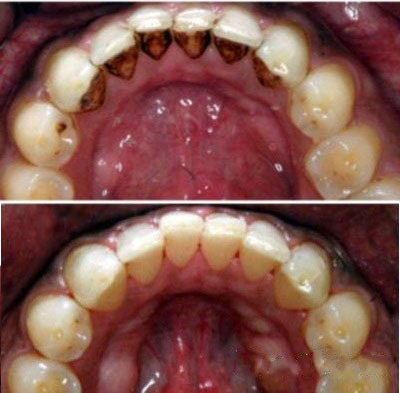

Зубной камень: фото до и после

Зубной камень — это затвердевший налет, который не был удален во время домашних процедур по уходу за полостью рта. Кроме эстетических проблем эти отложения способны доставить массу других неприятностей: они провоцируют различные стоматологические заболевания (кариес, гингивит, пародонтит) и в дальнейшем могут стать причиной потери зубов.